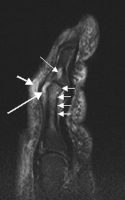

Magnetic resonance image of the index finger in psoriatic arthritis (mutilans form). Shown is a T2 weighted fat suppressed sagittal image. Focal increased signal (probable erosion) is seen at the base of the middle phalanx (long thin arrow). There is synovitis at the proximal interphalangeal joint (long thick arrow) plus increased signal in the overlying soft tissues indicating edema (short thick arrow). There is also diffuse bone edema (short thin arrows) involving the head of the proximal phalanx and extending distally down the shaft. -